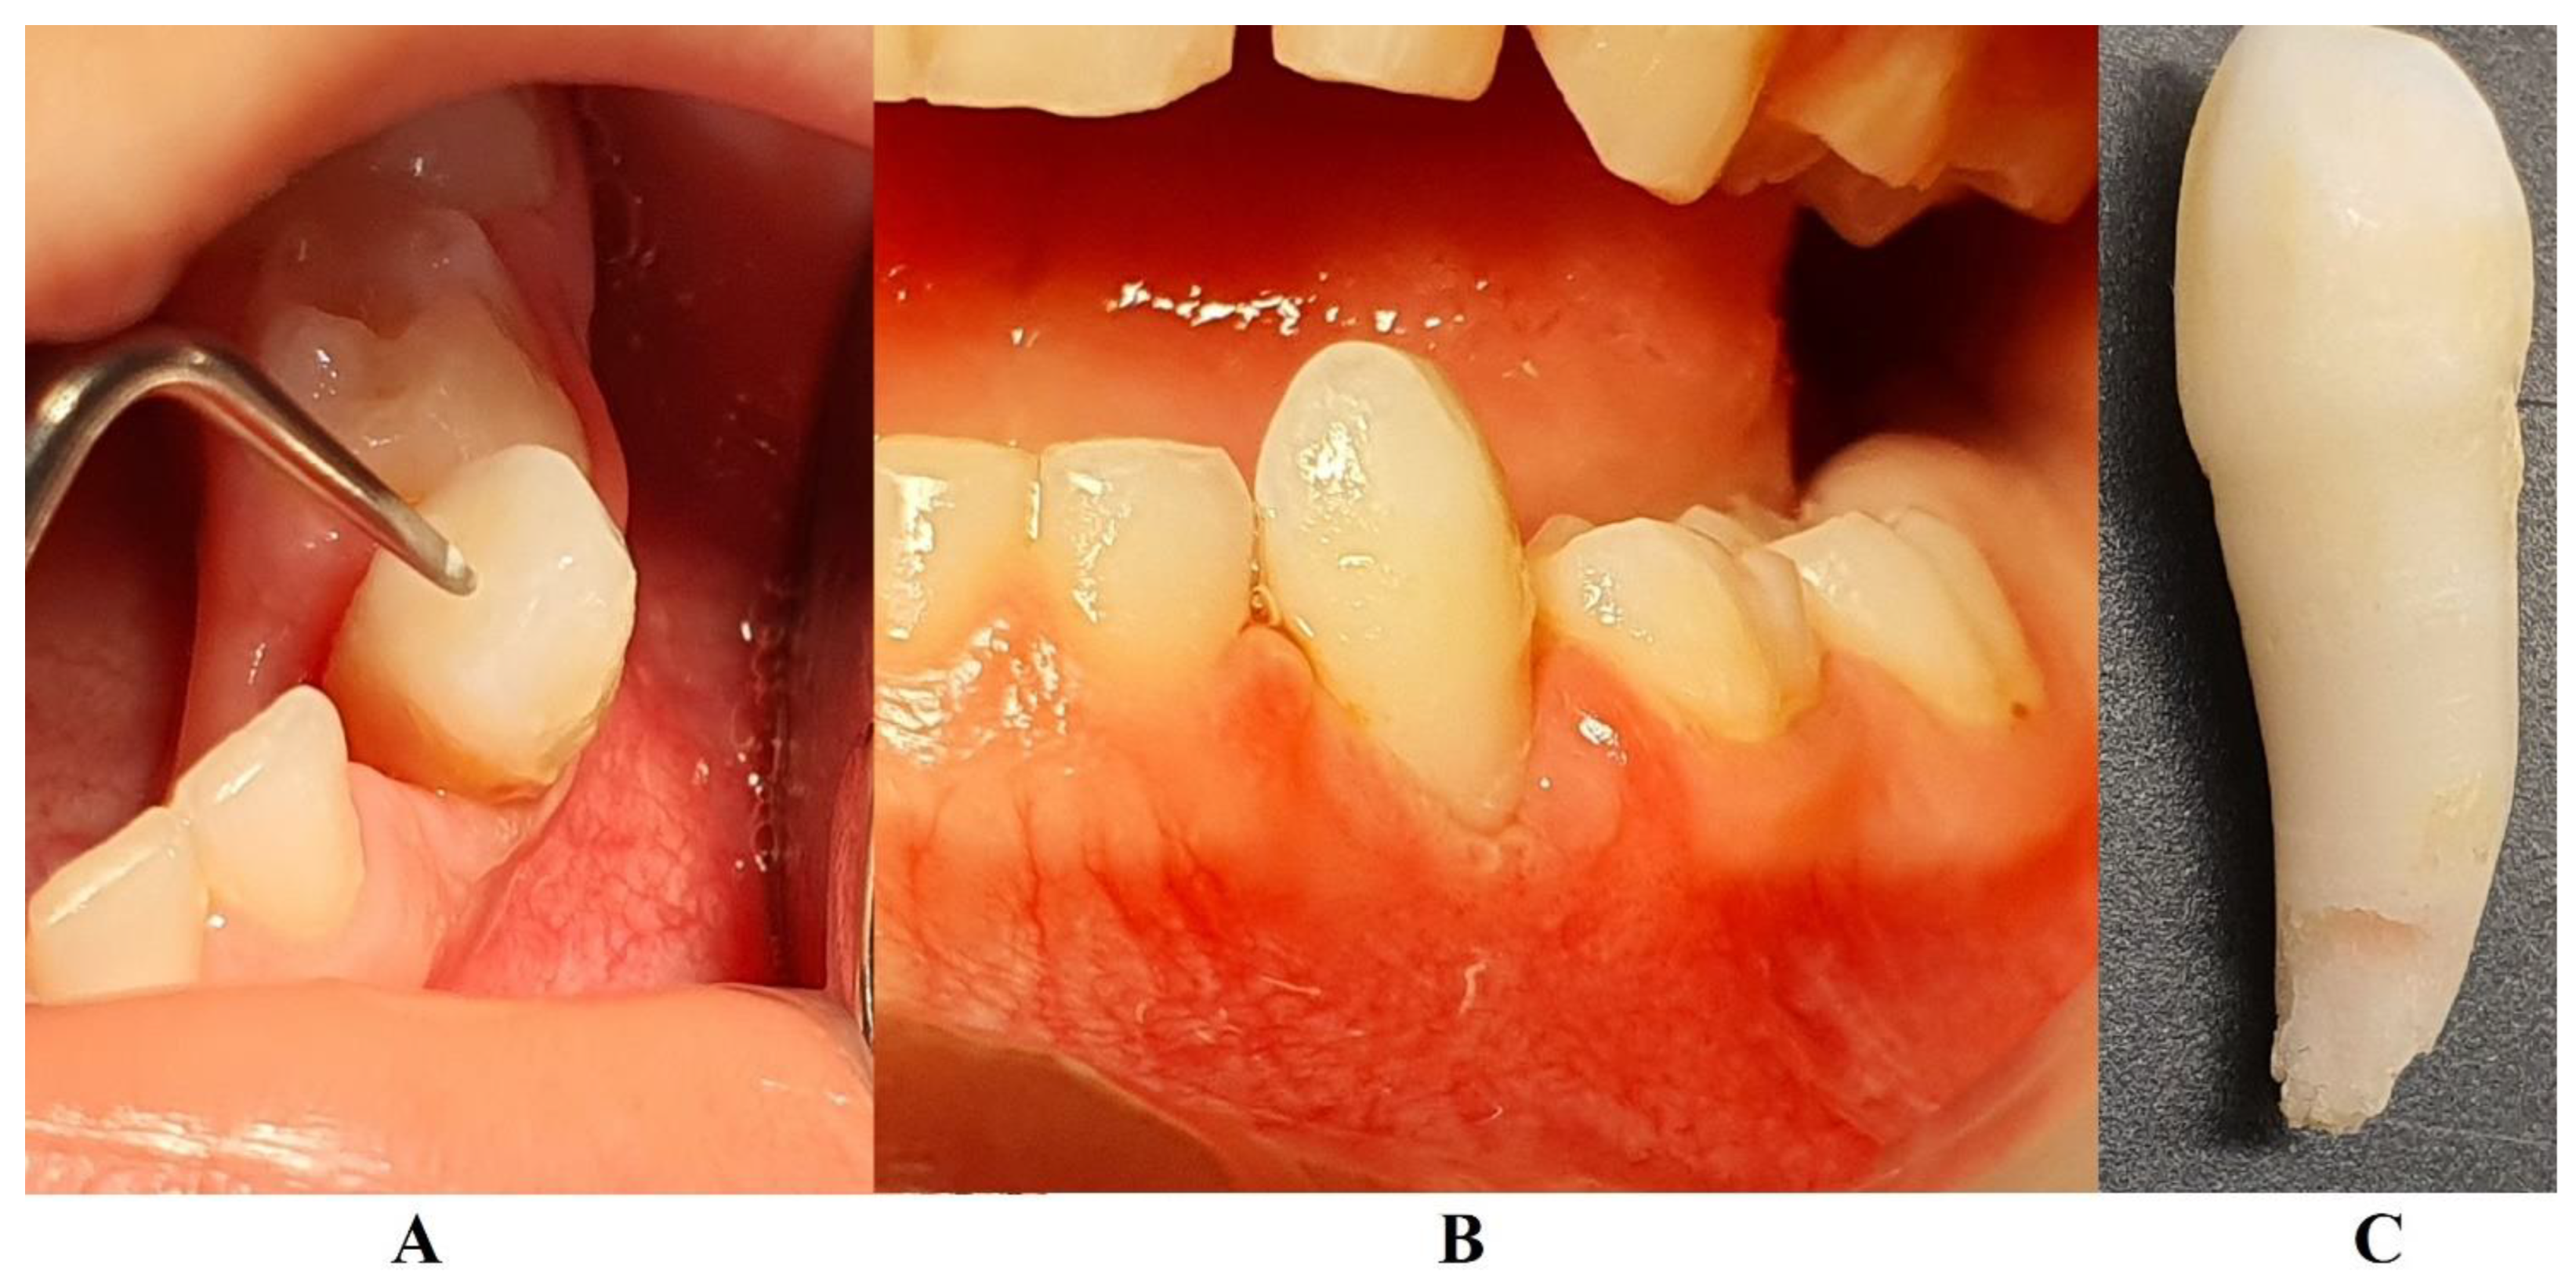

The family kept in touch with the clinician who diagnosed the LPP disorder informing about the case evolution, and in late December 2023 the family returned to Klausenburg (Cluj-Napoca – Romania). The panoramic x-ray (Figure 3) confirmed the presumed advanced periodontal loss around 8.3, but also bone loss around upper temporary canine and incisors (i.e., 5.3, 5.2 and 5.1), when compared with previous panoramic from June 2023 (Figure 1). Another investigated aspect was the lower left region of previous troubles, with no radiological signs of definitive canine sufferance (i.e., 3.3) and visible signs of bone regeneration. The oral clinical examination confirmed the lack of dental plaque and calculus, the advanced mobility of temporary lower canine, a light mobility of the other above-mentioned teeth and healing of the lost temporary lower left canine area (Figure 4). Another periodontopathic bacterial test was taken to reflect the latest bacterial types. Nevertheless, an oral professional cleaning was performed and based on previous LPP positive diagnosis, positive periodontopathic bacterial test and clinical evolution, a systemic antibiotic treatment was prescribed. The prescribed antibiotic (girl’s weight was about 15 kg) association was of Augmentin of 500 mg (1g/day, 1table twice a day) and Metronidazole of 250mg (500 mg/day, 1 table twice a day, but with the need to adjust the dosage if allergy/overdosed signs were to be displayed) for a period of 10 day, a periodontopathic bacterial test 2-3 months after the treatment ceased.

The periodontopathic bacterial test taken before the antibiotic prescription (i.e., late December 2023) came highly positive with five types of bacteria (when compared with only two types in the previous test received 16th of August 2023). Thus, besides the two types present in first test (i.e., 16th of August 2023) Fusobacterium nucleatum/periodonticum and Capnocytophaga already present in the oral cavity (and responsible for the loss of 7.3 and localized periodontal destruction) who remained highly positive, another three types showed up mildly positive: Treponema denticola, Eubacterium nodatum, Eikenella corrodens. Confirming not only the clinical worsening of the oral condition (Figure 3 and Figure 4), seen during oral examination (late December 2023) but also the chosen antibiotic association scheme.

In early May 2024 (i.e., 15th of May 2024) the family returned to Klausenburg (Cluj-Napoca – Romania), for a three-month control and evaluation. The clinical examination showed physiological mobility of all previous involved teeth, with no signs of periodontal inflammation and no plaque/calculus (Figure 5). No reports of pain complaints were reported (The last one being reported in October-November 2023). The panoramic radiological examination (Figure 6) showed a spectacular and visible periodontal regeneration and gain around 8.3 (that previously, in late December 2023, showed high periodontal loss), with visible periodontal gain around the upper and lower incisors. The definitive teeth showed physiological normality (especially the 3.3, closer to the periodontal loss site). A periodontopathic bacteria test was also taken (17th of May). The results (31st of May) revealed the presence of only “precursor germs of highly pathogenic ones” but with “no detectable highly pathogenic germs”. Nevertheless, the revealed precursor germs were those of Fusobacterium nucleatum/periodonticum, Campylobacter rectus, Eubacterium nodatum, Eikenella corrodens, and Capnocytophaga spp. The results at three months were considered to be favorable, meanwhile a 6 month’s control was scheduled for the autumn of 2024. However, up to early August 2024 (when herein report was written) no LPP reactivation signs showed up and no more pain complaints were reported.

The unusualness of this case is due to several aspects. The first is related to the extremely young age of the patient (i.e., 4 years-old in February 2023, temporary dentition), with an insidious onset, and apparently no familial aggregation or history. The second aspect is related to the misdiagnose to metabolic diseases (i.e., hypophosphatasia/hyperphosphatasia) despite the initial radiographical (i.e., Figure 1) and clinical examination that suggested a clear picture of an unusual LPP (e.g., the lower left canine involvement). The third aspect is related to the lack of therapeutic measures that rapidly set the course for the periodontal and 7.3 loss, in an interval of around 7 months (Figure 2) and the further progression involving other oral sites (Figure 3 and Figure 4). The fourth aspect is related to the evolution under adequate treatment (despite no written report to guide it) and the periodontal gain over a period of around 8 months following the antibiotic therapy (Figure 5 and Figure 6).

The natural periodontal gain observed in this case is important from the prognosis point of view. It was observed that the site of the lost 7.3 showed periodontal gain (i.e., Figure 3, the panoramic form early January 2024), in the absence of the correct antibiotic association (since solely Augmentin did not cover all pathological bacterial types). However, it must be emphasized that it cannot be predicted the impact on this matter of the above-mentioned incorrect antibiotic treatment performed in October 2023 (i.e., no signs of other periodontal gain on upper and lower incisors and only progression of the periodontal loss around the 8.3). Nevertheless, significant periodontal gain was observed on the last panoramic (Figure 6, May 2024) after the correct antibiotic association.

Figure 3. Panoramic x-ray radiological investigations with advanced periodontal loss around the temporary lower right canine, and periodontal gain around temporary lower left canine site (late December 2023) (Klausenburg, Romania).

Figure 4. Images of the oral status in late December 2023: A – 8.3. localized lingual gingival inflammation, B – maxillary teeth, C – lower left canine site with signs of periodontal gain.